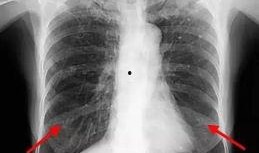

最近在网上看到一个超级劲爆的消息,就是2023年的胸片爆料最新版大揭秘!这可是医学界的一大喜事,咱们得好好聊聊这个话题。你有没有...